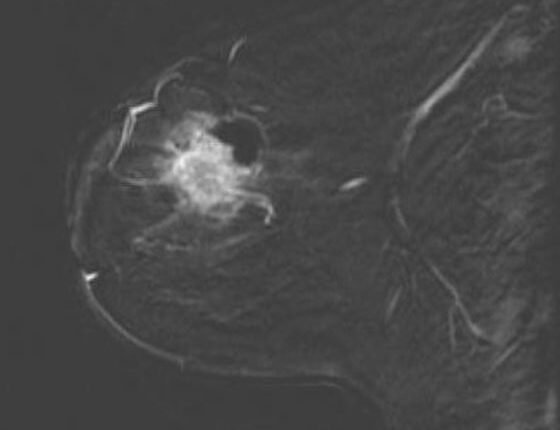

Η τομογραφία των μικροκυμάτων είναι σε θέση να ξεχωρίσει τον καρκίνο του μαστού, τους καλοήθεις όγκους και τον φυσιολογικό ιστό.

Οκτώ γυναίκες με καρκίνο του μαστού υποβλήθηκαν σε αγωγή με χημειοθεραπεία ως μέρος της κανονικής θεραπείας τους, μέχρις ότου υποβληθούν σε χειρουργική επέμβαση. Κατά τη διάρκεια της θεραπείας, η μαγνητική τομογραφία συμπληρώθηκε με τομογραφία μικροκυμάτων στο Dartmouth-Hitchcock Medical Center.

Περιοχές υψηλής αγωγιμότητας αντιστοιχούσαν με τους όγκους, αυτές της χαμηλής αγωγιμότητας αντιστοιχούσαν στους φυσιολογικούς ιστούς και σε αντίθεση με άλλες τεχνικές απεικόνισης, ο δείκτης μάζας σώματος, η ηλικία ή η πυκνότητα του μαστού δεν φαίνεται να επηρεάζει τα αποτελέσματα. Αυτή η τεχνική απεικόνισης είναι χαμηλού κόστους και μπορεί να επαναληφθεί σε πολλά στάδια κατά τη διάρκεια της θεραπείας.

Ο Πολ Μίνεϊ από το Dartmouth College, ο οποίος ηγήθηκε της μελέτης εξηγεί: «Kαλώντας τις ασθενείς για τις σαρώσεις κατά τη διάρκεια της θεραπείας τους, διαπιστώσαμε ότι μπορούσαμε να δούμε πραγματικά τους όγκους να συρρικνώνονται σε γυναίκες που ανταποκρίθηκαν σε χημειοθεραπεία. Η τομογραφία μικροκυμάτων θα μπορούσε επομένως να χρησιμοποιηθεί για να εντοπίσει τις γυναίκες που δεν ανταποκρίνονται στην αρχική θεραπεία, ούτως ώστε αυτή να αλλάξει κατάλληλα σε πρώιμο στάδιο».